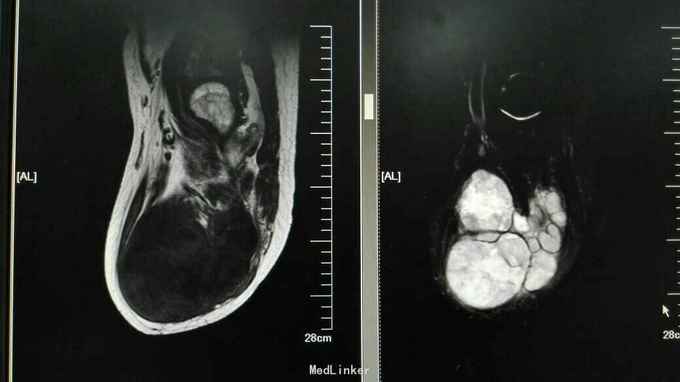

查体:右膝稍肿胀,皮温正常,右膝髌上囊处压痛(+),右膝屈曲稍受限(0~100度),余查体正常。 辅助检查:血常规、ESR、CRP正常 膝关节正侧位片:右膝关节退行性变,髌上囊肿胀 膝关节MRI提示:右膝髌上囊软组织占位,侵犯至股四头肌,考虑滑膜肉瘤可能性大 关节镜取活检提示滑膜肉瘤 全身PET-CT未见其它部位转移,肺无转移

诊断:右膝关节滑膜肉瘤 治疗:右大腿中上段截肢术